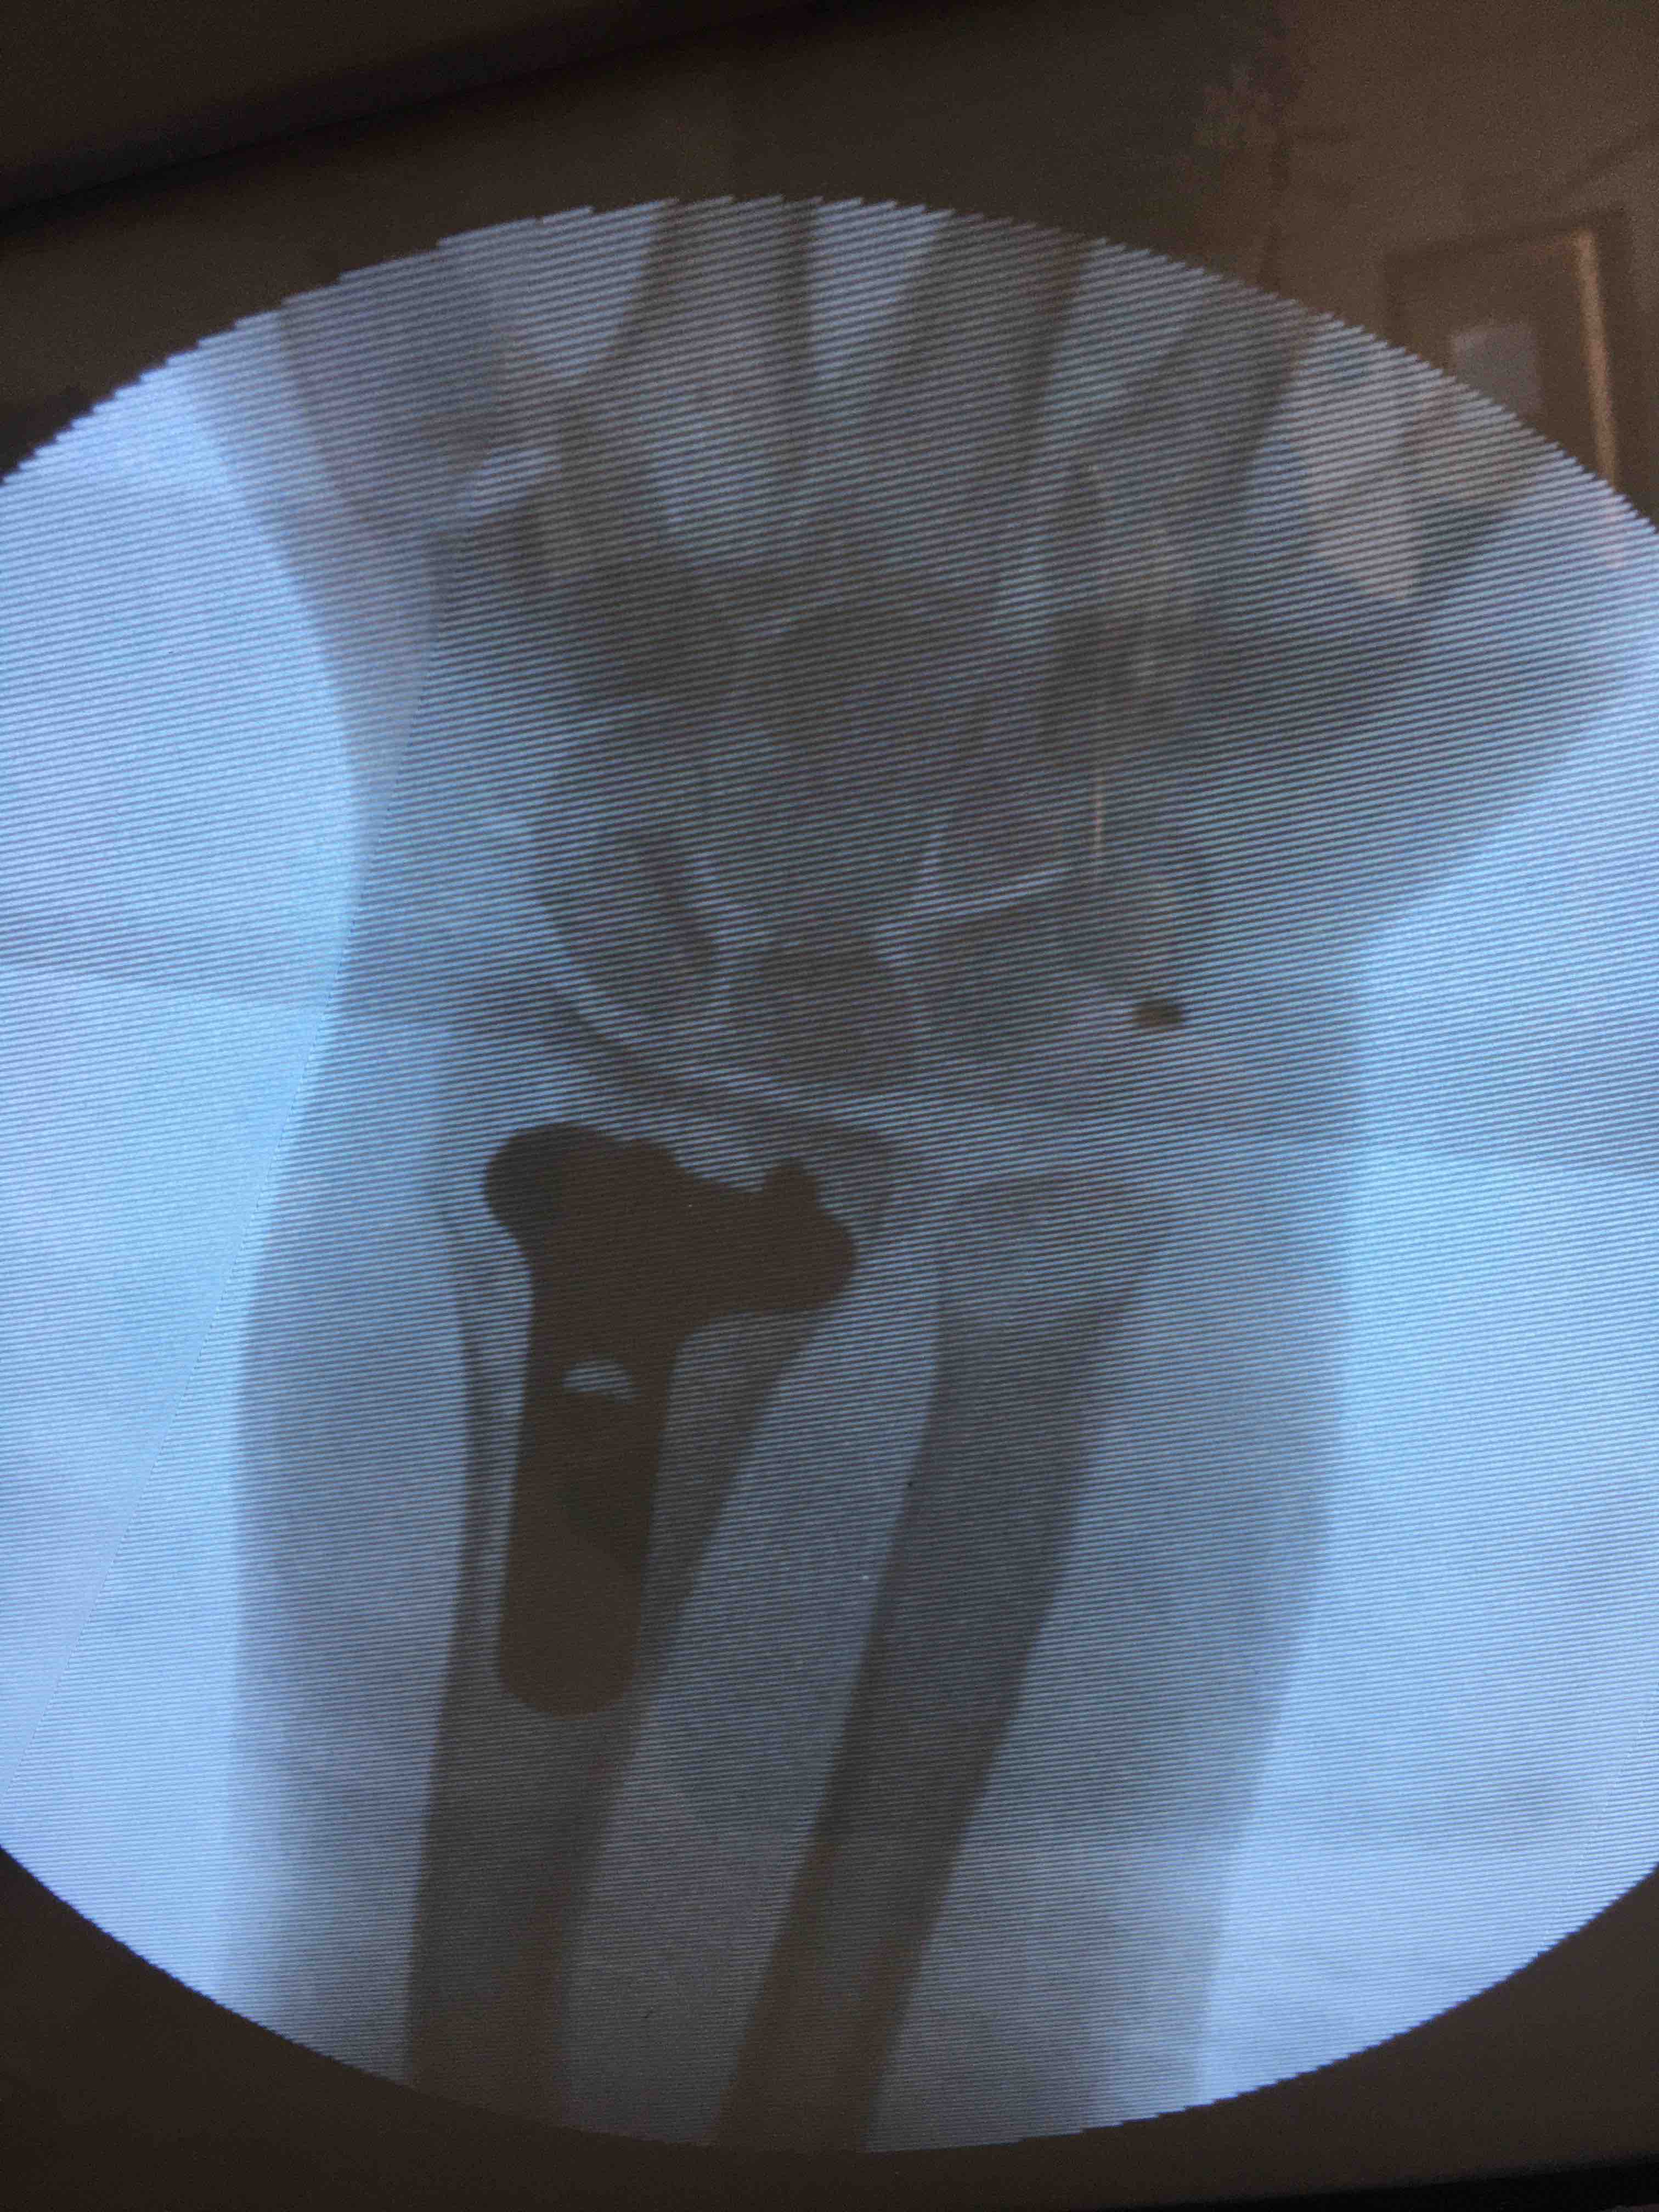

生命体征平稳,心肺复未见异常。左腕部肿胀明显,局部皮色皮温正常,畸形,压痛及纵向叩击痛阳性,腕关节活动受限,感觉血运正常。

诊断左colles骨折

在臂丛下行切复内固定术,术后抗炎消肿等处理。